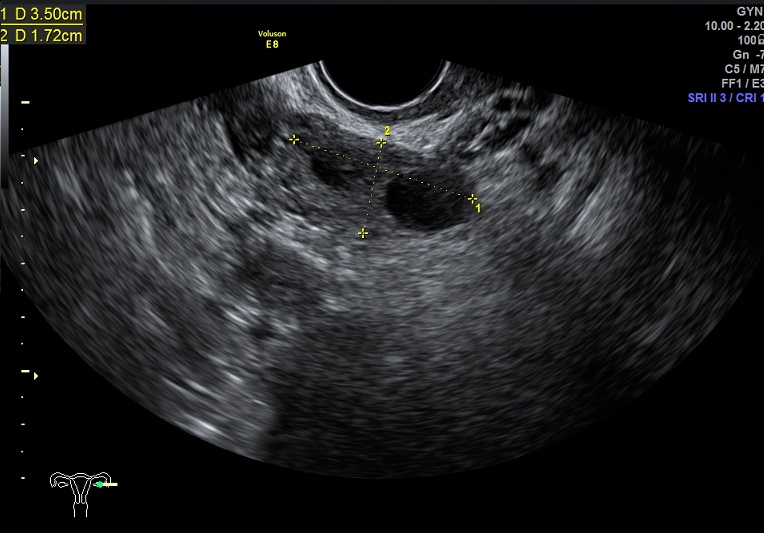

左卵巢: 大小3.5x2.0x1.7cm 体积:6.2 窦卵泡:无 左卵巢见两枚大卵泡:1.9x1.2x1.0cm、1.5x1.2x1.1cm 卵巢间质血流:9.8cm/s RI:0.49